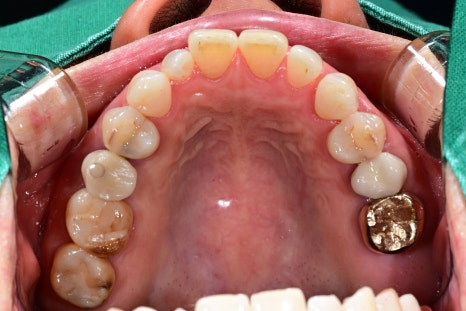

⑤ 최종 치아(크라운) 제작 및 장착

회복 후 구강스캐너로 본을 떠

개인 맞춤형 크라운을 제작합니다.

서울오브치과병원은 치과기공사가 상주하고 있어

제작과 수정이 빠르고 정밀한 것이 특징입니다.

합리적인 임플란트 가격에 수술이 가능하고

해당 환자분도 최종 보철 장착 후

“원래 내 치아 같은 느낌”이라고 말씀하셨습니다.